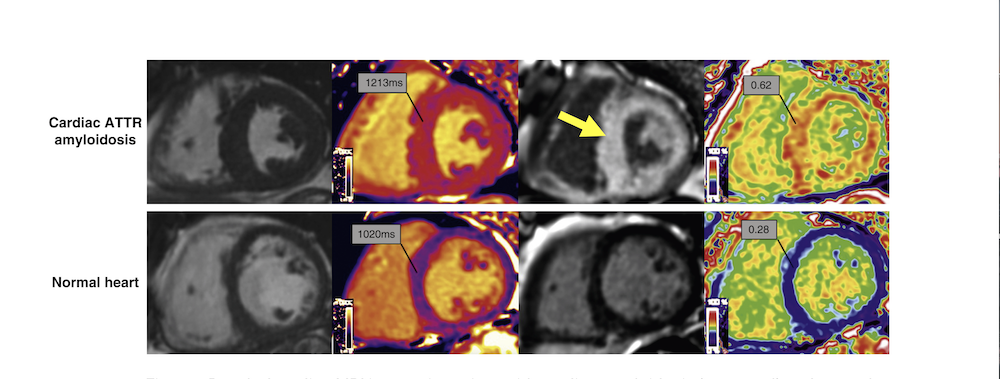

CMR parametric mapping techniques such as T1 mapping, T2 mapping and Extra Cellular Volume (ECV) provide useful insight for assessment of diffuse fibrosis in CA, FD and HCM. T1 mapping technique quantifies the heart muscle's T1 relaxation time pixel-by-pixel, creating color-coded maps to assess tissue health. T1 relaxation time is measured in millisecond (ms) in each pixel in the myocardium and is a fundamental property of heart tissue that changes with pathology.

As a parametric map different colors represent different T1 values, allowing for precise quantification, unlike standard MRI contrast images. Parametric T1 mapping is typically performed in combination with LGE imaging, acquired before and after injection of GBCA (with and without contrast agent). One of the key properties of GBCA is to modify T1 values of tissues and any changes in T1 values (depends on the concentration of GBCA in the tissue) can be captured on parametric maps. ECV, a measurement of the size of the extracellular space, is calculated from native (pre-contrast) and contrast enhanced T1 values of myocardium and blood as well as patient’s hematocrit. ECV is elevated in amyloidosis and other infiltrative diseases, due to the expansion of extravascular space from amyloid deposits but in their absence, it is a biomarker for myocardial fibrosis.